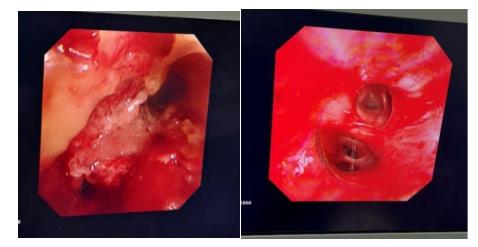

病灶切除前后对比:左主支气管被肿瘤完全阻塞(左),肿瘤切除后左主支气管完全通畅(右)

病灶切除前后对比(左图为术前,右图为术后)